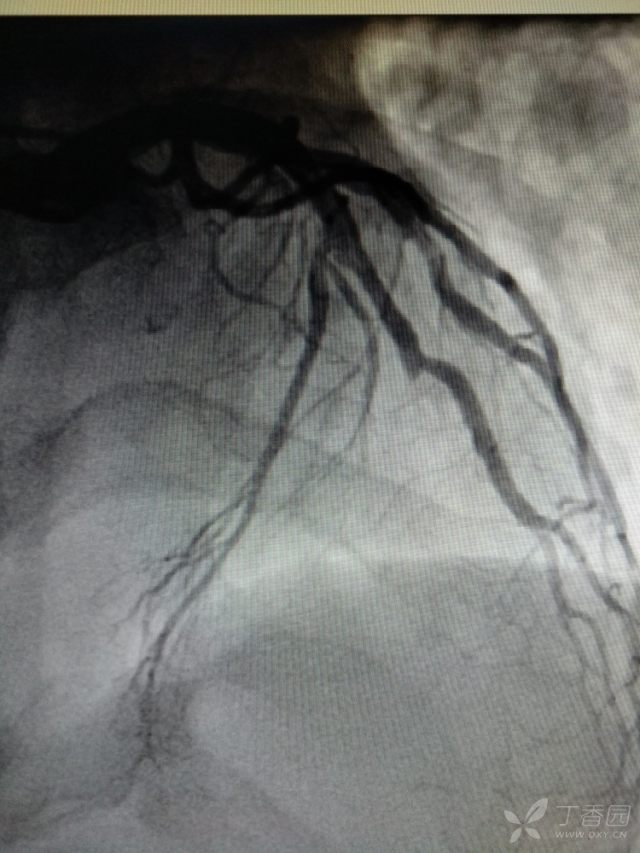

下面这些是急性心肌梗死的患者的心电图和造影的对比图,看见这些心电图要及时作出诊断。